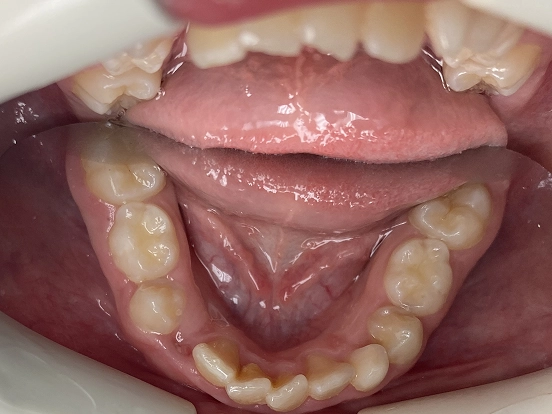

Braces EJ

EJ’s braces journey demonstrates how traditional orthodontics can deliver a complete and lasting smile transformation. The braces effectively corrected spacing and bite issues, leaving behind a perfectly straight, radiant smile that reflects months of dedication.